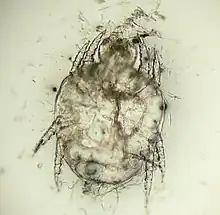

"Cheyletiella yasguri" (?) from a dog

Cheyletiella yasguri (?) from a dog

The adult mites are about 0.385 millimeters long, have eight legs with combs instead of claws, and have palpi that end in prominent hooks.[5] They do not burrow into the skin, but live in the keratin level. Their entire 21-day life cycle is on one host. They cannot survive off the host for more than 10 days.[6]